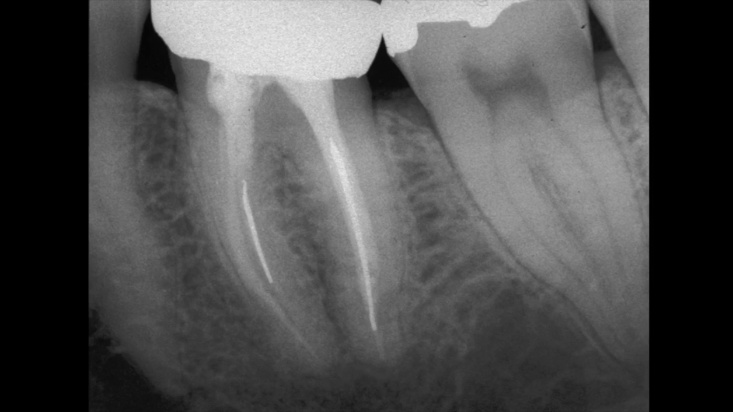

Сл. 37.38 Безбедно отстранување колче со навој од дисталниот канал на долниот лев втор молар. а) Предоперативна радиографија. б) Колчето со навој е отстрането. в) Контрола по шест месеци. Референтниот стоматолог ставил ново колче со навој и пак во мезијалниот корен!